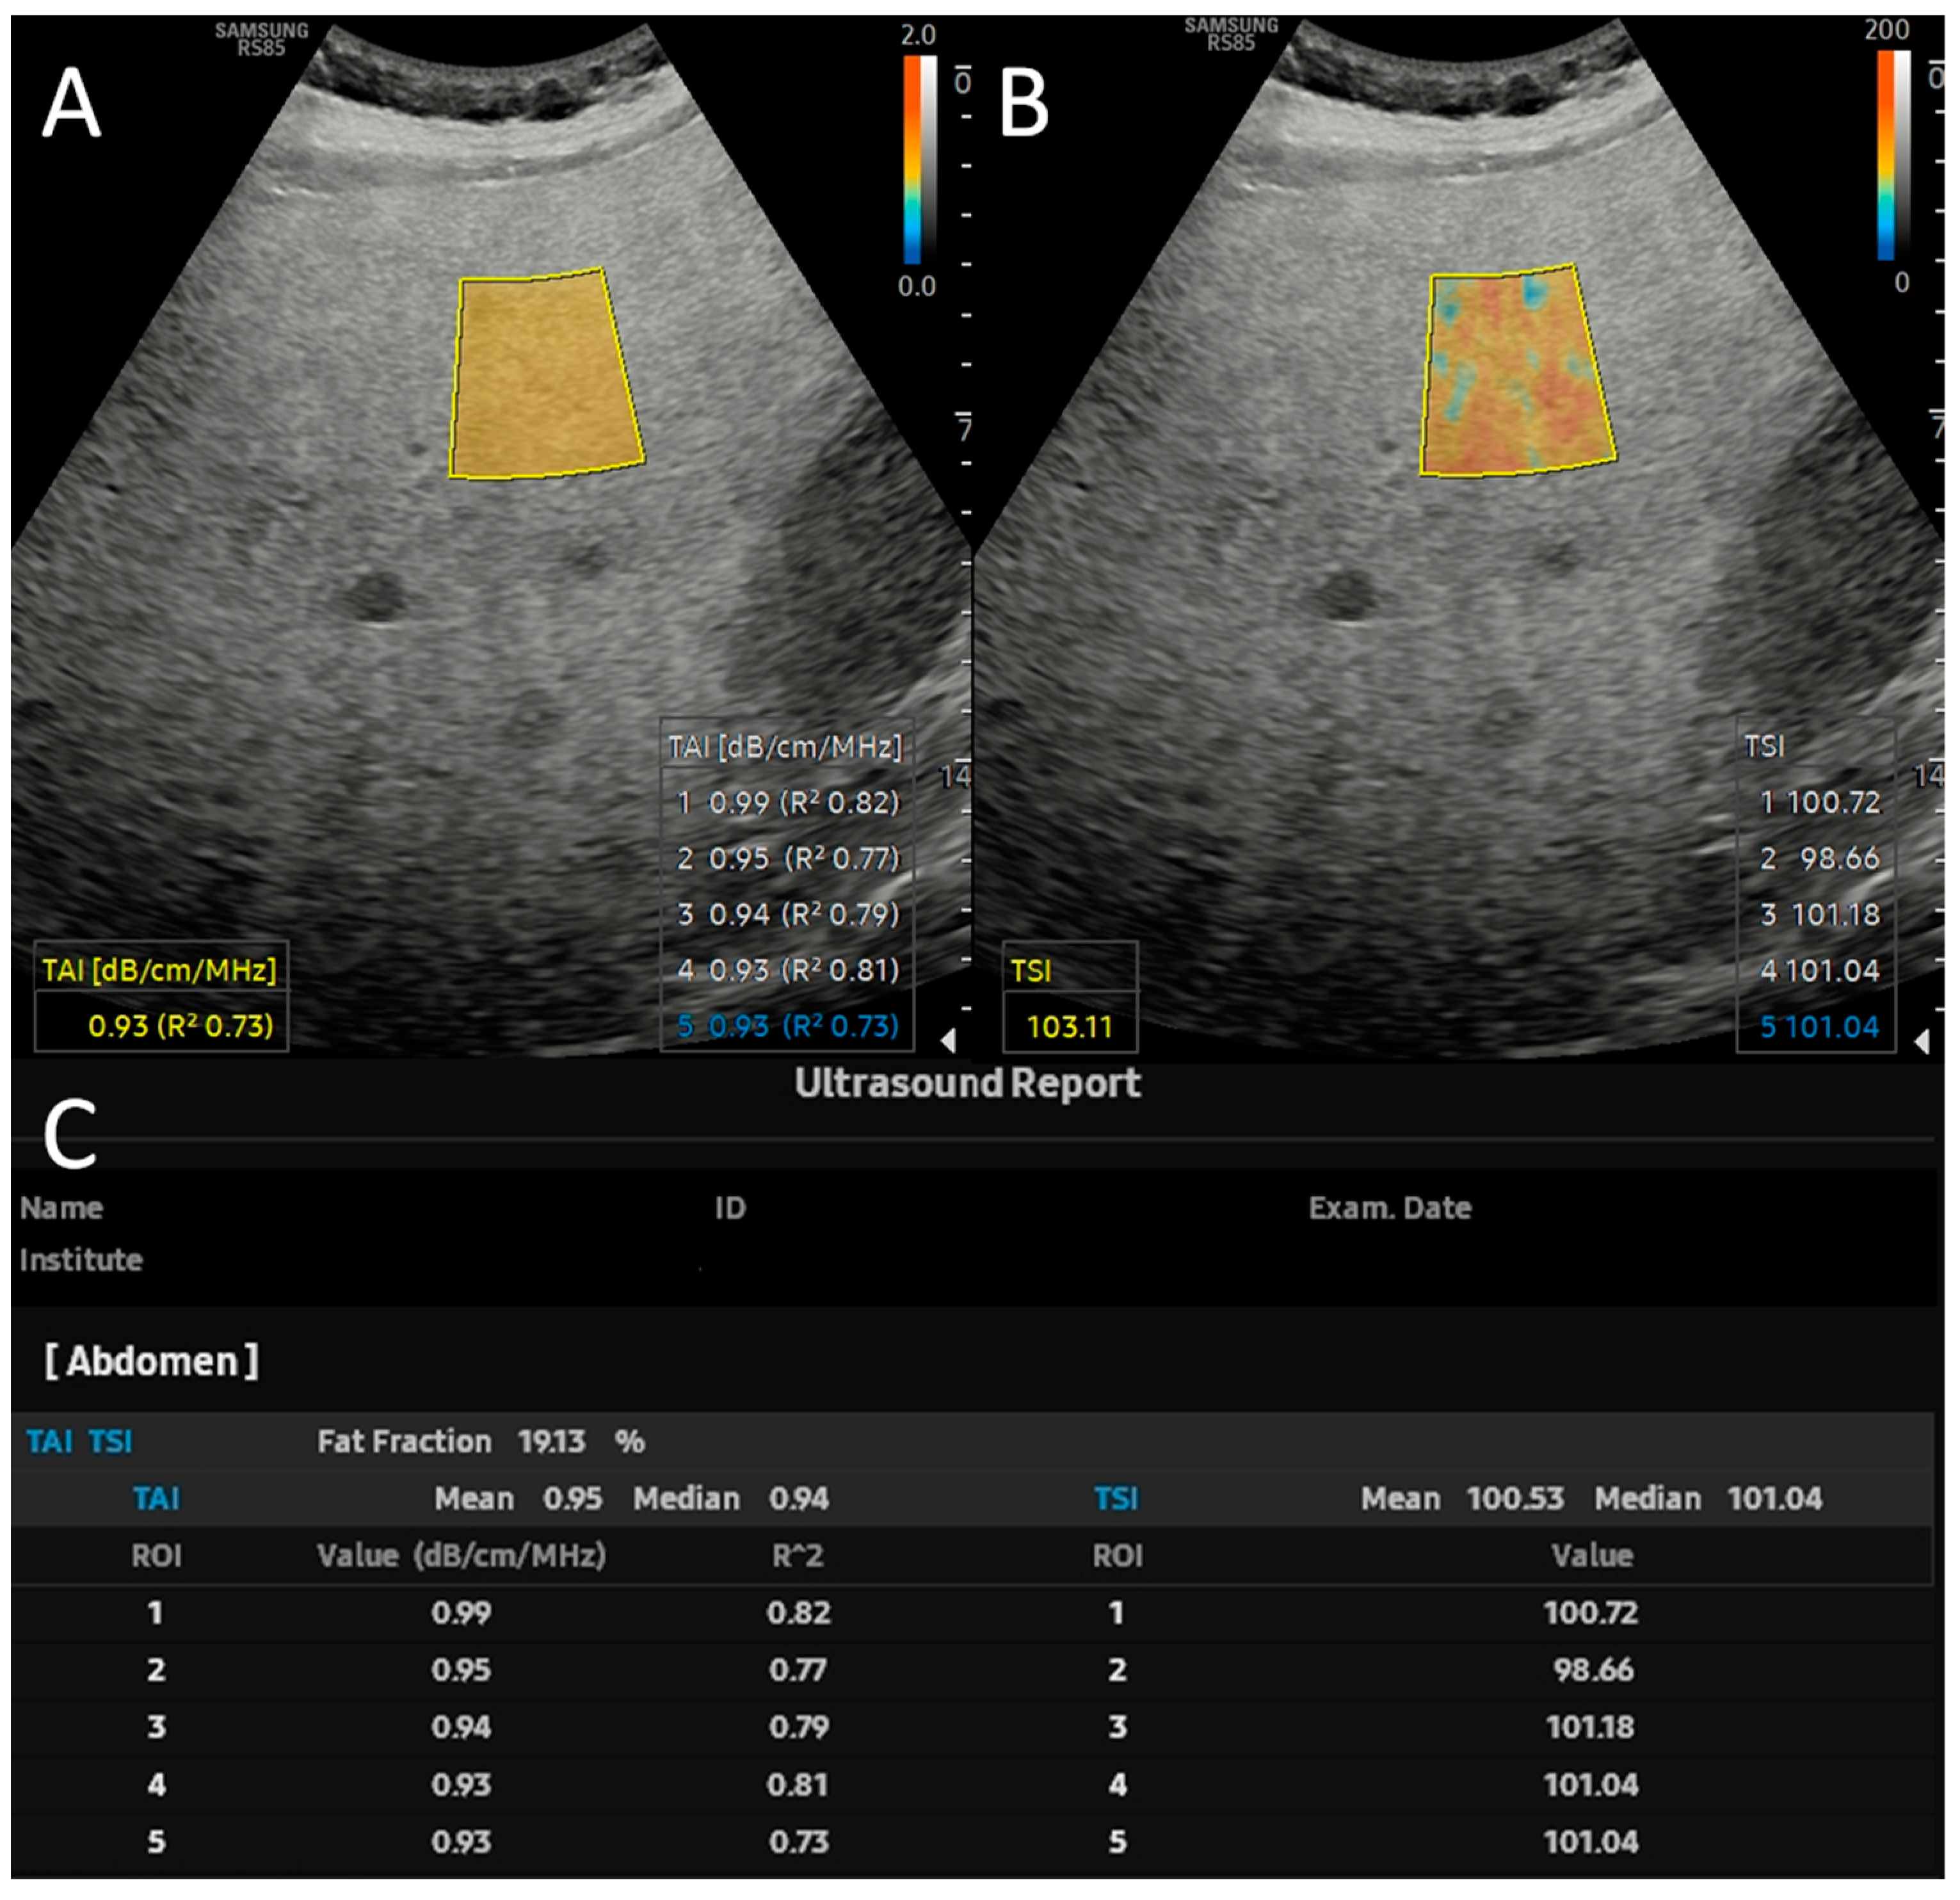

2.2. Quantitative Ultrasound and USFF Measurements

3.2. Variable Selection and Training of Models